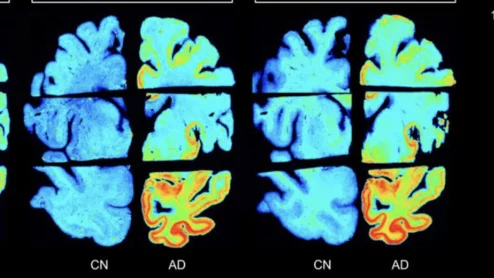

Video of Jamshid Maddahi, MD, UCLA, explaining why flurpiridaz will change cardiac imaging and increase the adoption of PET cardiac imaging.

The newly approved PET radiotracer is expected to improve patient care significantly. “We have been able to reach the pinnacle of myocardial perfusion imaging with flurpiridaz," one expert said.